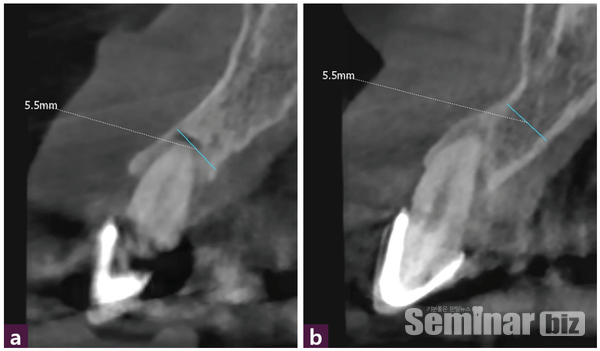

CBCT 진단에서 12번과 22번 치아의 협측 골 판과 구개측 골 판이 50% 이상 소실된 증등도 이상 치주질환임을 확인할 수 있다 [그림 3].

12, 22번 발치 후 GPS Drill을 이용해 구개측에 Magic Guide Pin을 삽입하고 [그림 4] CBCT 촬영 후 진단한 결과 12번은 순측의 gingiva에서 5.5mm, 22번은 순측의 gingiva에서 5 mm의 공간을 확보할 수 있었다.